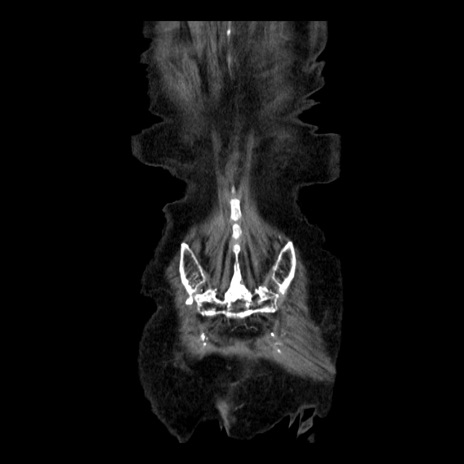

症例14(冠状断像)

症例

【症例】 90歳代女性

【主訴】 腹痛・嘔吐

【現病歴】今朝から左側腹部痛を認めた。 経過観察していたが、嘔吐を認めたため来院。

【既往歴】 子宮癌術後

【身体所見】 意識清明、BP 127/54mmHg、P 98bpm Sp02 95%(RA)、BT 35.8°C、腹部平坦・軟腸ぜん動音聴取良好、右下腹部圧痛(+) 反跳痛なし

【データ】WBC 9800、CRP 0.46